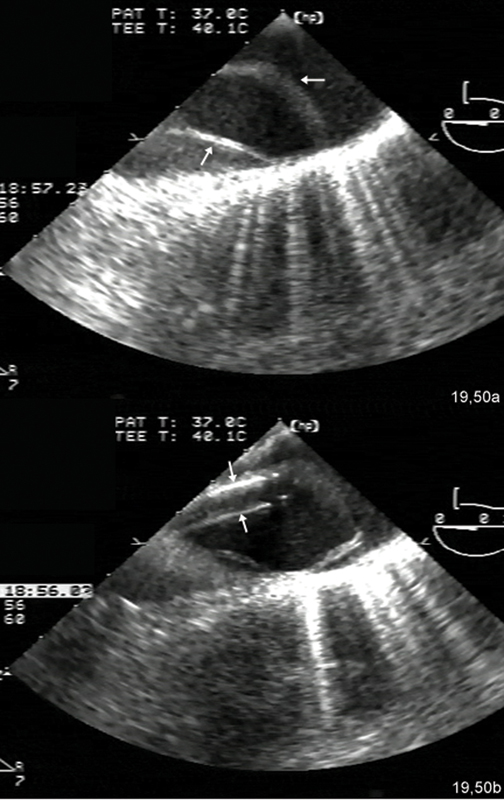

فحوصات تشخيصية لبعض امراض القلب والشرايين التاجية